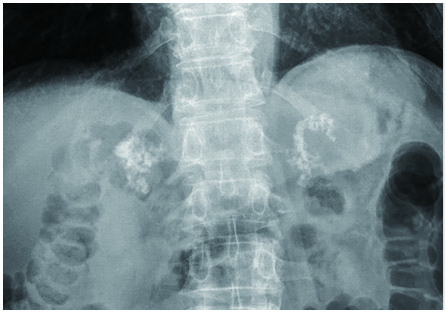

【答案公布】看图诊断,这张CT有何异常?